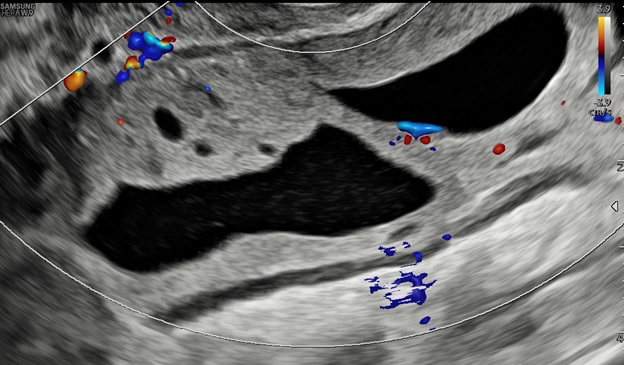

– Siêu âm: Tử cung và 2 buồng trứng bình thường. Ở cùng đồ sau có cấu trúc echo kém không đồng nhất dạng hình ống, có vách ngăn dày thông nhau, kích thước # 84x 89x 37 mm, bờ trong thành u không trơn láng, bên trong có nhiều mảng echo kém dạng mô đặc, tăng sinh mạch máu mức độ 2. Bụng và cùng đồ: không dịch.

– Chẩn đoán siêu âm: Huyết tụ thành nang. Chẩn đoán khác: áp xe phần phụ.

Hình 5: Siêu âm ngã âm đạo cho thấy thành u có tăng sinh mạch máu độ 2